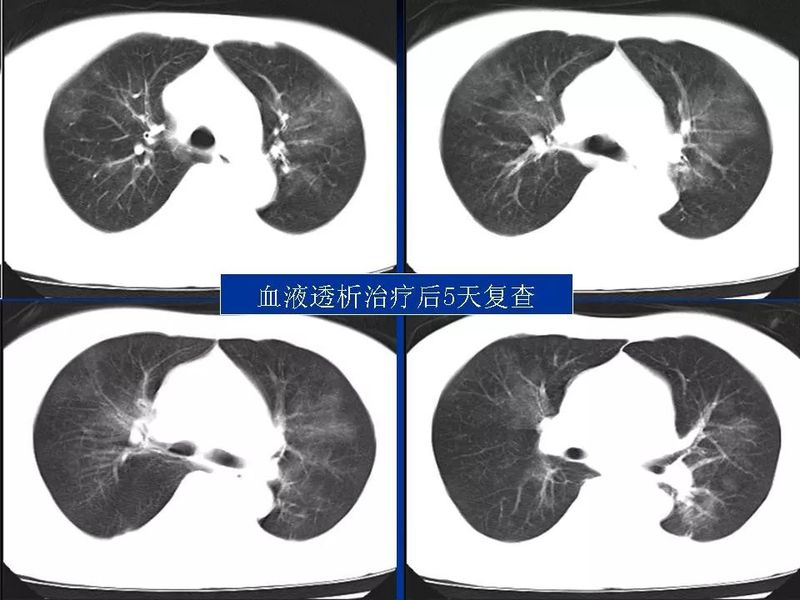

主任提醒:这个病很容易误诊为肺炎!